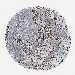

SKIN CANCER - Protein expressioni

A mouse-over function shows sample information and annotation data. Click on an image to view it in a full screen mode. Samples can be filtered based on level of antibody staining by selecting one or several of the following categories: high, medium, low and not detected. The assay and annotation is described here.

Antibody stainingi

Antibody staining in the annotated cell types in the current human tissue is reported as not detected, low, medium, or high, based on conventional immunohistochemistry profiling in selected tissues. This score is based on the combination of the staining intensity and fraction of stained cells.

Each image is clickable and will lead to virtual microscopy that enables deeper exploration of all samples and also displays staining intensity scores, fraction scores and subcellular localization as well as patient and tissue information for each sample.

Antibody HPA018038

Antibody HPA020762

Staining

High

Medium

Low

Not detected

Intensity

Strong

Moderate

Weak

Negative

Quantity

>75%

75%-25%

<25%

None

Location

Nuclear

Cytoplasmic/membranous

Cytoplasmic/membranous,nuclear

Squamous cell carcinoma in situ, NOS

Squamous cell carcinoma, NOS

Squamous cell carcinoma, metastatic, NOS

Basal cell carcinoma